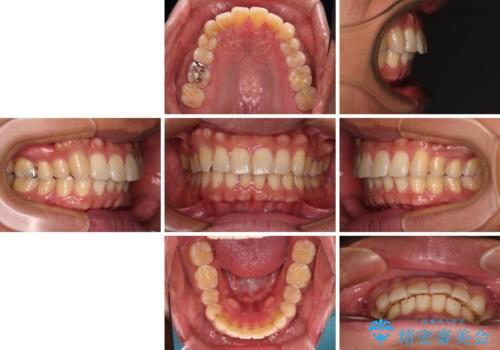

- 20代男性

- インビザライン

- 4年8ヶ月

- 前歯のデコボコを気にして来院された患者様です。

当院でインビザライン矯正治療をされている方からのご紹介ということで、インビザラインでの矯正治療をご希望でした。

ワイヤー矯正に比べ来院頻度は低いものの、新幹線での通院のため、やや治療期間が延びることが懸念されました。

配属異動や長時間勤務などによりインビザラインが十分に装着できない期間があり、インビザライン有効期限5年間ギリギリとなってしまいました。

- 矯正治療後の保定が不十分だと後戻り(元の位置に戻ろうとする動き)をします